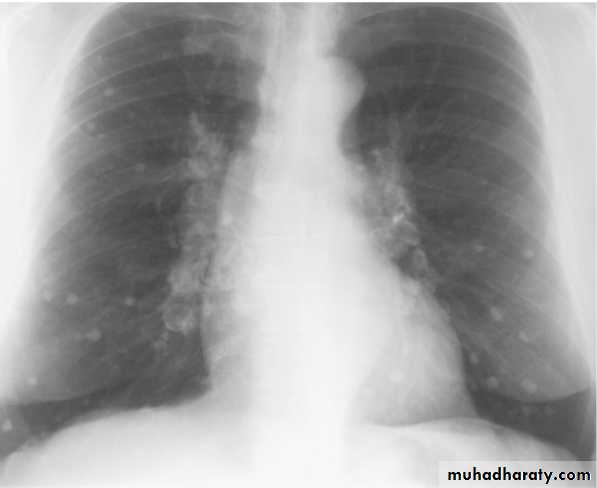

Differential diagnosis of multiple spherical lesions:

1 - Metastasis.

2-Hydatid cyst.

3- Sarcoidosis.

4- Rheumatoid nodules.

5 – pneumoconiosis

6- Histoplasmosis